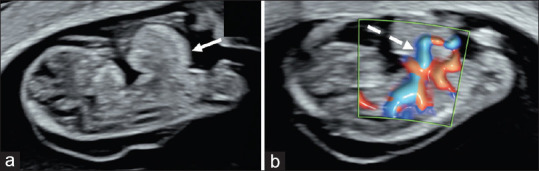

A Pattern of Malformations in the First Trimester Ultrasound.